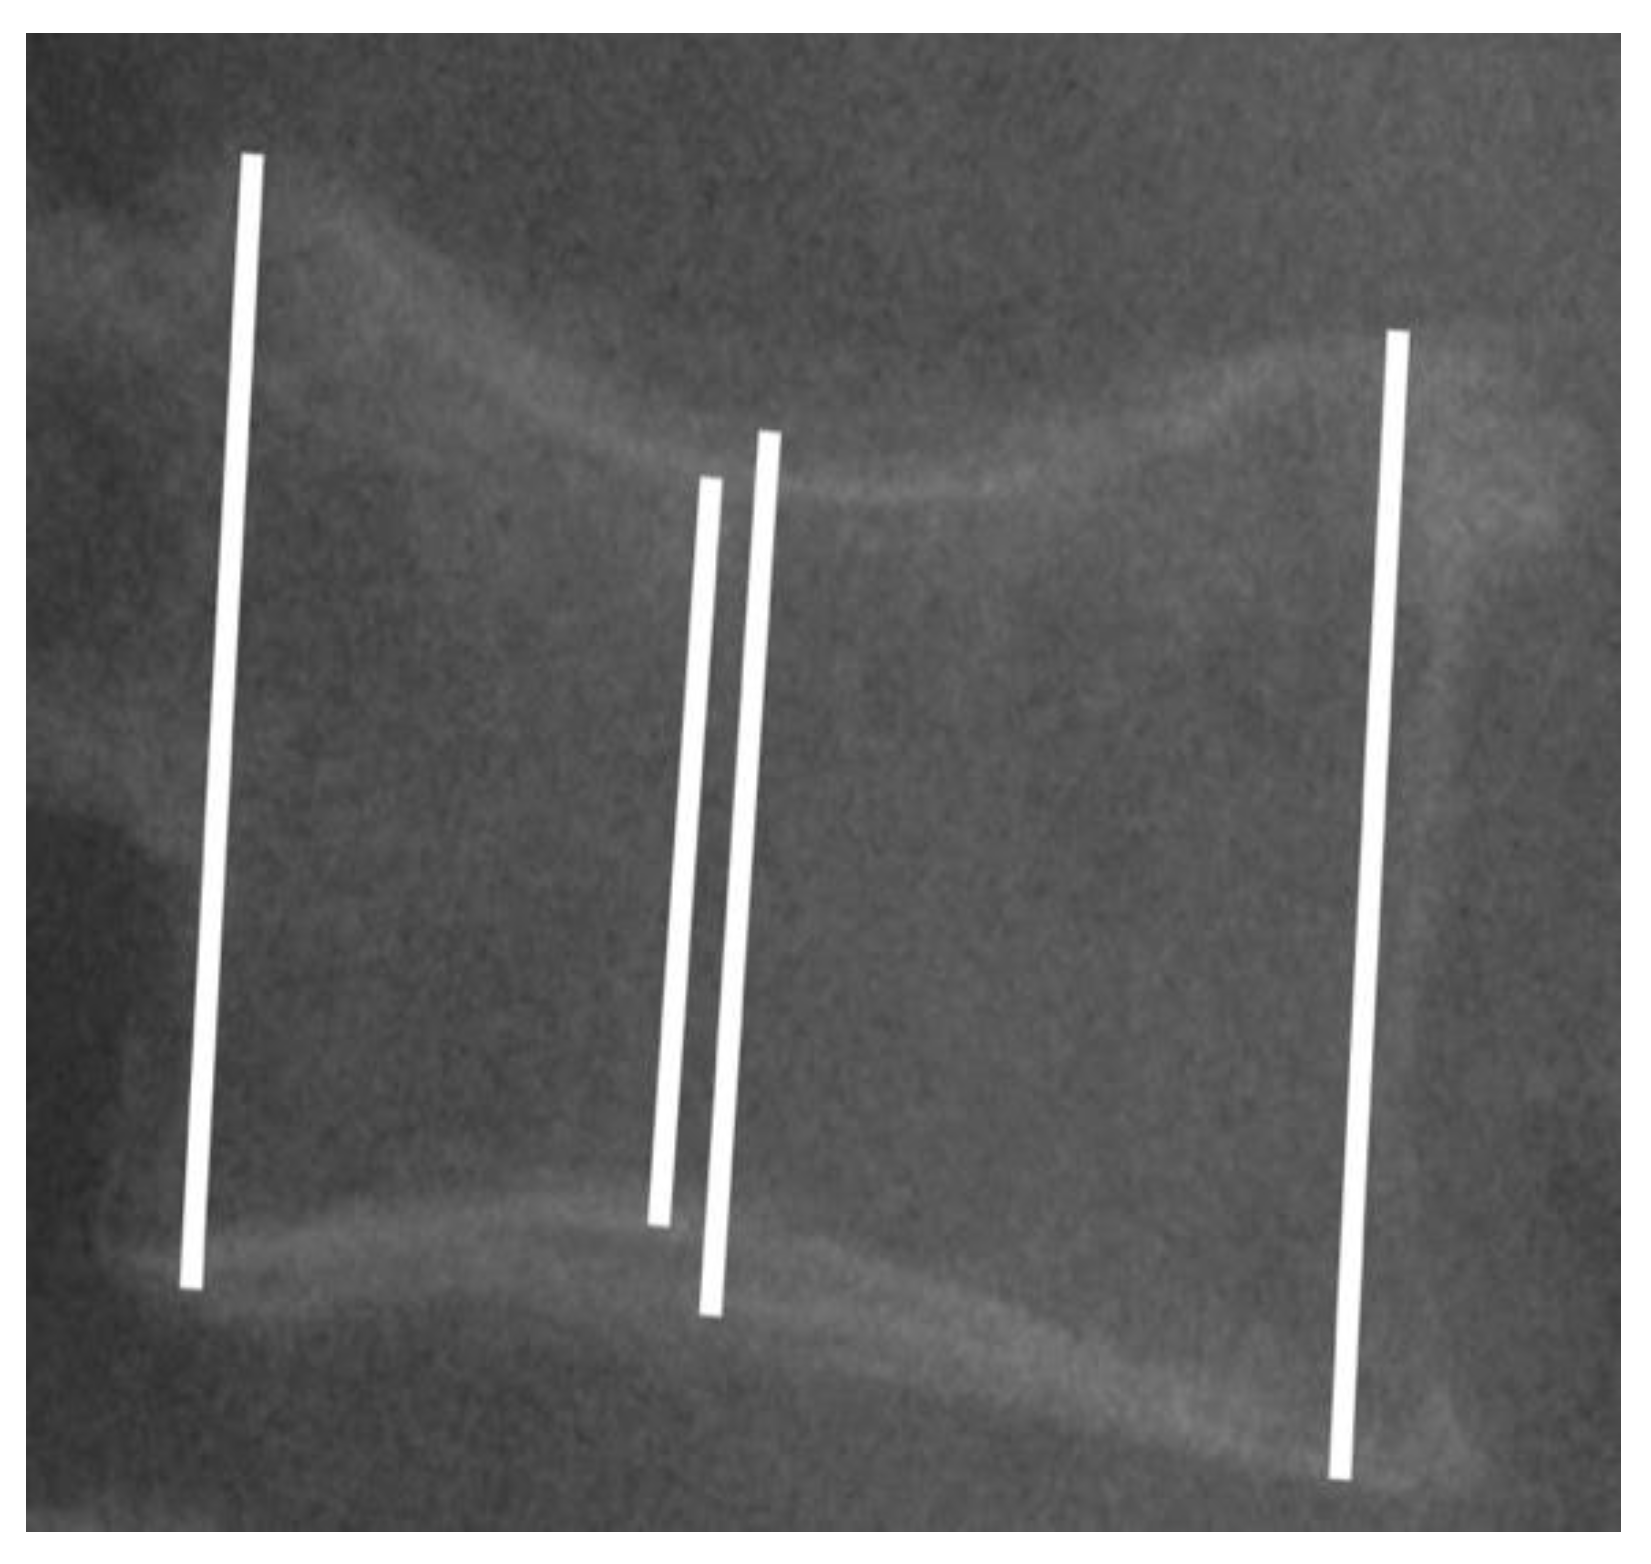

3.2. Radiological Measurement